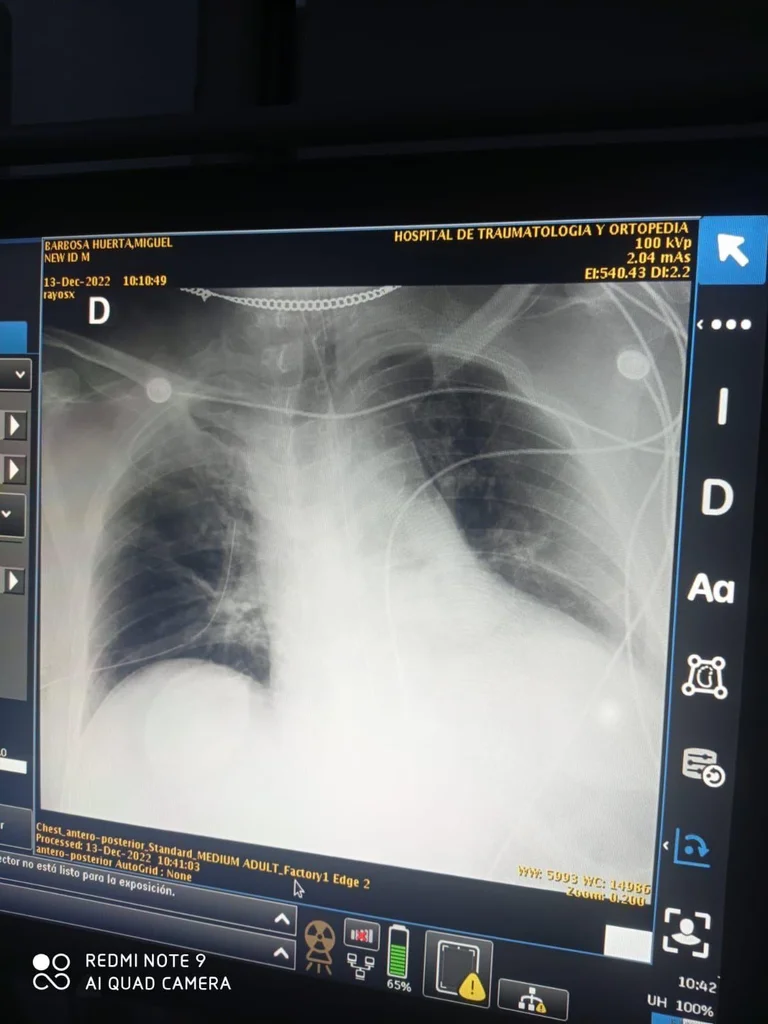

Sin embargo, más tarde el periodista Claudio Ochoa Huerta, quien escribe para Latinus, reveló a través de sus redes sociales que tuvo contacto con personas involucradas en los hechos, quienes le aseguraron que hubo varias negligencias y le compartieron la fotografía de una radiografía anteroposterior de tórax que comprobaría el supuesto.

La siguiente presunta negligencia aparentemente ocurrió al revisarlo en el Hospital de Ortopedia, pues le habrían hecho un mal procedimiento que terminó por perforarle el pulmón que aparece del lado izquierdo de la radiografía. Según el periodista se lo “poncharon”.

Cabe subrayar que el procedimiento que presuntamente “ponchó” el pulmón del exgobernador habría sido para detener un neumotórax. La Clínica Universidad de Navarra (CUN) señala que el padecimiento ocurre cuando hay fugas de aire en el espacio entre los pulmones y la pared torácica, que puede hacer que el pulmón colapse, por lo que requiere atención inmediata.

Para ser tratado, los médicos deben confirmar el estado de los pulmones con una radiografía y aplicar alguna de las técnicas médicas disponibles, entre las que se encuentran la introducción de talco o tetraciclinas para producir adherencias, la cirugía, así como la inserción de una sonda torácica, la cual puede ser muy riesgosa.